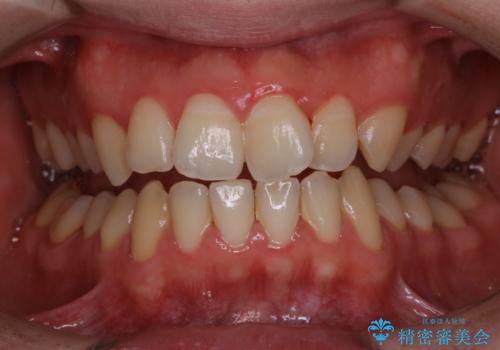

- 今まで歯医者で、クリーニングを受けたことがないため綺麗にしたいとのことでした。PMTC60分コースを行いました。

もっとも、効果的な治療法がPMTC(歯科医院で専門的な機械や材料を使用してクリーニング)を定期的に行うことです。

表参道しらゆり歯科 DH西澤